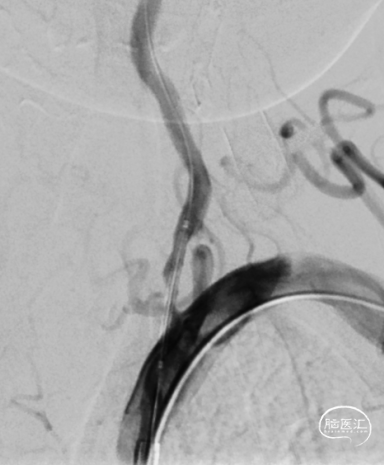

沿微导丝送入3.0mm*16mm Bridge椎动脉雷帕霉素靶向洗脱支架到达目标位置。经手推造影确认定位后,缓慢加压释放支架。

随访:患者术后一般情况好,无TIA再次发作。神经系统查体无明显异常,血压控制良好。

该患者双侧椎动脉起始段均狭窄,左侧更为严重,为闭塞前病变。为预防致死致残性脑卒中,行左侧椎动脉起始段支架植入术。选择Bridge椎动脉雷帕霉素靶向洗脱支架。该支架的雷帕霉素涂层可向血管内膜靶向释放药物,有效抑制支架植入术后的内膜增生,减少远期支架内再狭窄几率。同时也能有效改善后循环的血供,减少后循环脑卒中发生机会。该支架是治疗椎动脉狭窄的良好选择。